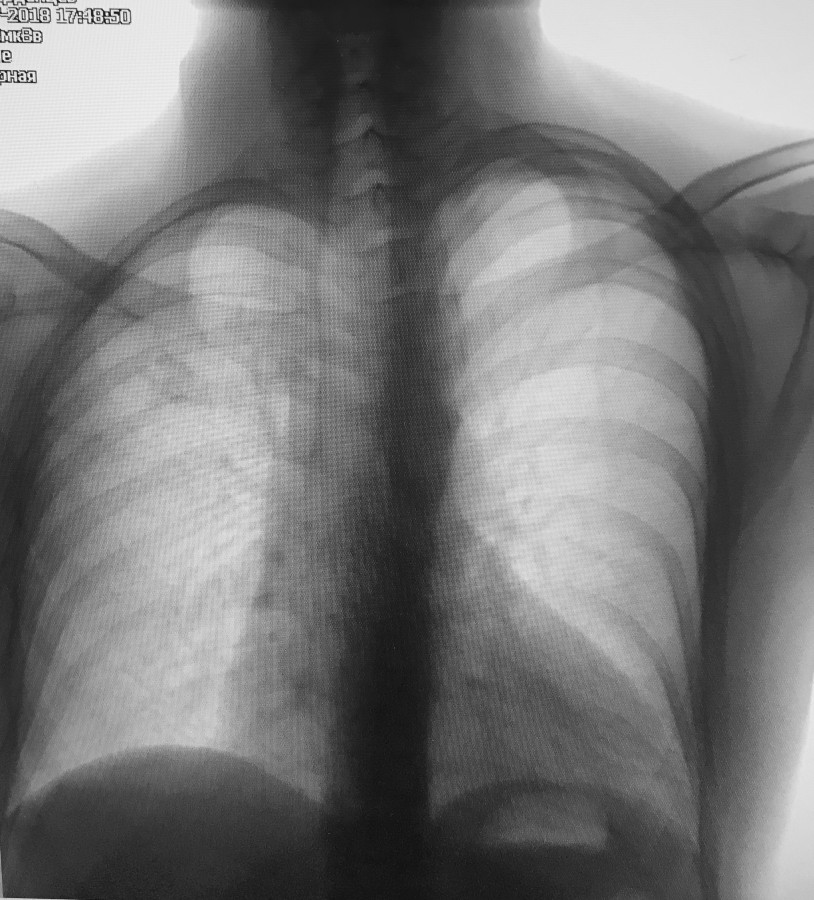

Заголовок сообщения: Марфан. Расслоение аорты.

М 32 года.